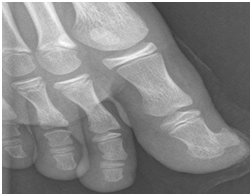

A 12-year-old boy presented at our Institution with right toe pain and swelling with six months of evolution. The patient also presented a progressive increase in pressure sensation. He had no history of trauma prior to the emergence of the symptoms. On physical examination, the terminal extremity of the second toe was swollen, without any other signs such as heat or erythema. The nail plate was elevated, hyperkeratotic and thickened. The toe mobility, sensibility and vascularity were normal. Radiographs showed a heavily calcified mass on the terminal phalanx of the first toe, which was attached to the underlying cortex (Figure 1). There were no signs of periosteal reaction and no alteration of the underlying bone to which the lesion was attached. In this sense, a presumptive diagnosis of subungual exostosis was made and we decided to perform its surgical resection. We decided to perform a subungual approach, lifting the nail plate, which allowed a dorsal view of the terminal toe phalanx. An “en-bloc” resection of the lesion and a decortication of the underlying bone were performed. We have also removed the portion of the nail which presented alterations.

Figure 1 Radiography: a heavily calcified mass on the terminal phalanx of the first toe, which was attached to the underlying cortex.